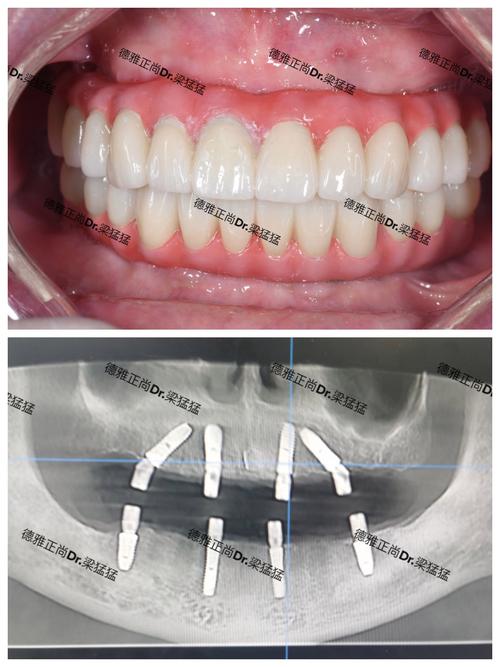

半口/全口牙缺失种植修复:

- 案例描述: 这是种植牙技术最具革命性的应用之一,针对半口或全口缺牙:

- All-on-4/6技术: 利用4颗或6颗 strategically placed 种植体,支撑起半口或全口的固定牙桥,当天或短期内即可戴牙,实现即刻负重,大大缩短治疗周期和等待时间。

- 种植覆盖义齿: 利用2-4颗种植体安装磁性或球帽附着体,使活动假牙获得更稳固的固位和更好的咀嚼力,同时保留一定的活动性(便于清洁)。

- 固定全口种植桥: 利用足够数量的种植体(通常6-8颗以上)支撑一个固定的、不可摘除的全口牙桥,提供最接近天然牙的稳定性和舒适度。

- 特点: 技术含量高,对医生团队、设备、材料要求极高,南京的大型公立医院和高端私立口腔机构是这类案例的主要承担者,能提供从传统到即刻负重、从覆盖义齿到固定桥的多种解决方案。